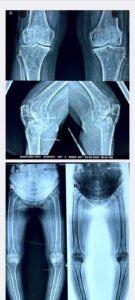

उन्होंने बताया कि मरीज को दोनों घुटनों में असहनीय दर्द और चलने-फिरने में कठिनाई रहती थी। 16 सितम्बर को उसे ट्रॉमा सेंटर में भर्ती कर आवश्यक जांचें—एक्स-रे, स्केनोग्राम, MRI और थायरॉइड जांच—की गईं। इसके बाद निर्णय लिया गया कि मरीज के दोनों घुटनों का एक साथ प्रत्यारोपण किया जाएगा, ताकि उसे जल्दी से जल्दी सामान्य जीवन जीने का अवसर मिल सके। 19 सितम्बर को सम्पन्न हुई इस सफल सर्जरी के बाद मरीज अब स्वस्थ है और शीघ्र ही अपनी दैनिक दिनचर्या में लौट सकेगी।